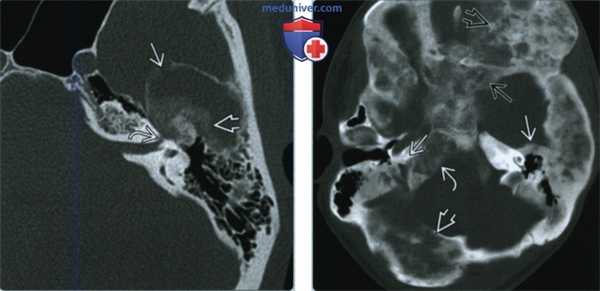

(Слева) При КТ в костном окне в корональной проекции определяется утолщенная чешуя височной кости неоднородной плотности. Также наблюдается утолщение клиновидной кости неоднородной плотности. В теле нижней челюсти определяется преимущественно кистозный (фиброзный) очаг поражения.

(Справа) При аксиальной КТ в костном окне у этого же пациента с полиоссальной фиброзной дисплазией определяются смешанные рентген прозрачные и склеротические изменения кости. Обратите внимание: шов резко разграничивает зоны различных изменений кости, что характерно для фиброзной дисплазии.